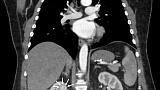

Иллюстрация №7: Рис. 6. Компьютерная томография в МГОБ № 62: стрелочками показана опухоль правой почки.

По данным компьютерной томографии органов грудной клетки и брюшной полости с контрастным усилением: состояние после гастрошунтирующей операции, умеренно выраженная внутрибрюшная и забрюшинная лимфаденопатия (лимфоузлы до 10 мм), в верхнем полюсе правой почки опухоль до двух сантиметров в диаметре (рис. 6).